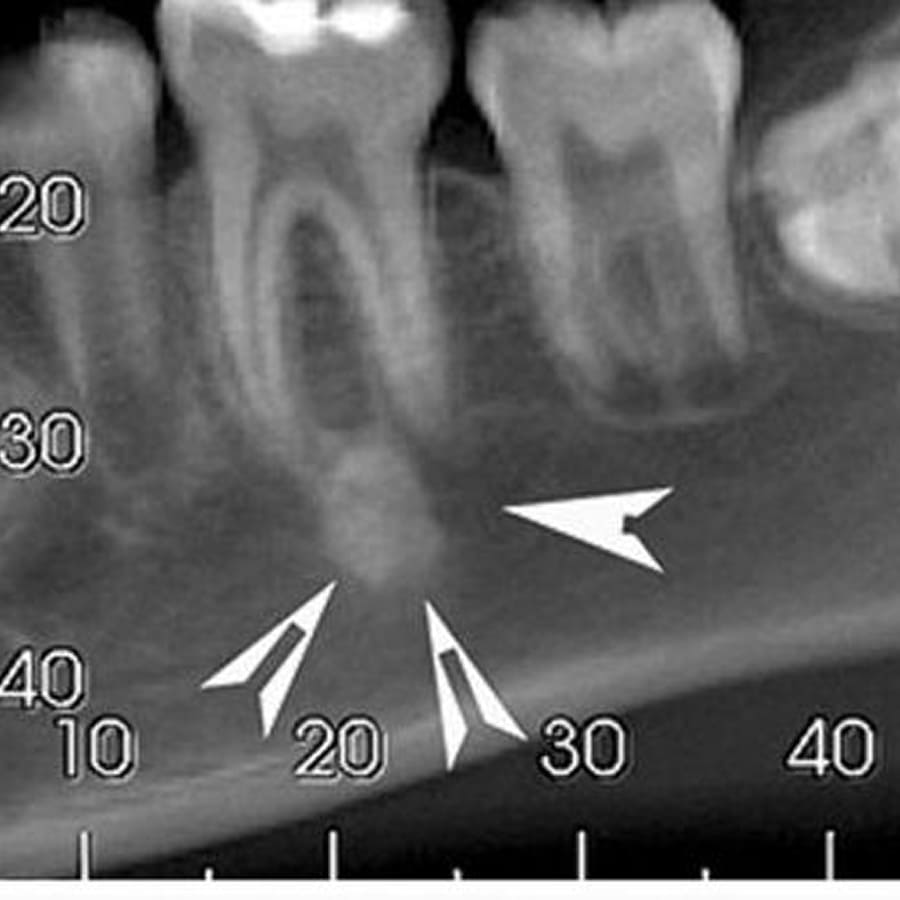

Essas intervenções são planejadas com base em diagnóstico clínico, exames de imagem e avaliação minuciosa da patologia odontológica envolvida — seja inflamação, fratura, infecção, alterações ósseas ou condições que comprometem a mordida.

Antes do procedimento, o dentista realiza uma avaliação clínica detalhada. Depois, podem ser necessárias:

radiografias ou tomografias

análise da patologia ou condição bucal